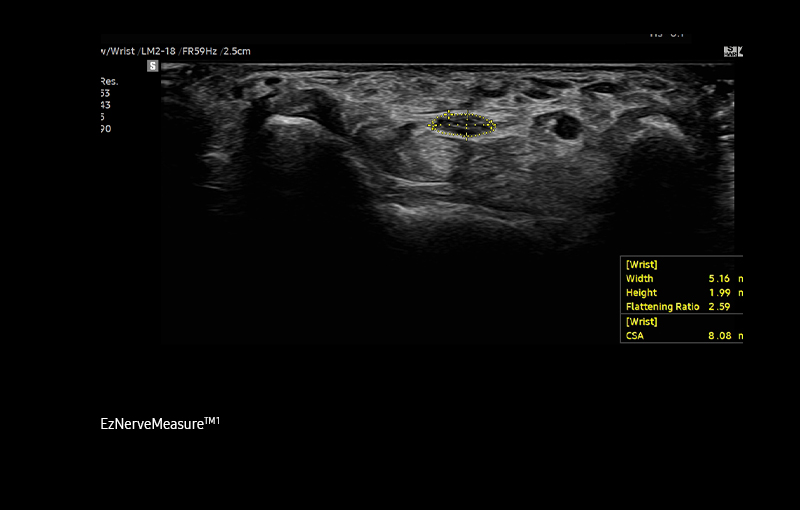

A semi-automated

measurement tool for nerve

EzNerveMeasure™ ¹ is a feature that provides measurement results

of the long axis, short axis, flattening ratio, and Cross-Sectional

Area of the detected nerve area.

Detect and track nerves with

AI technology

NerveTrack™ ¹ , a feature based on Deep Learning technology,

detects and provides information of the location of the nerve area

in real-time during ultrasound scanning.